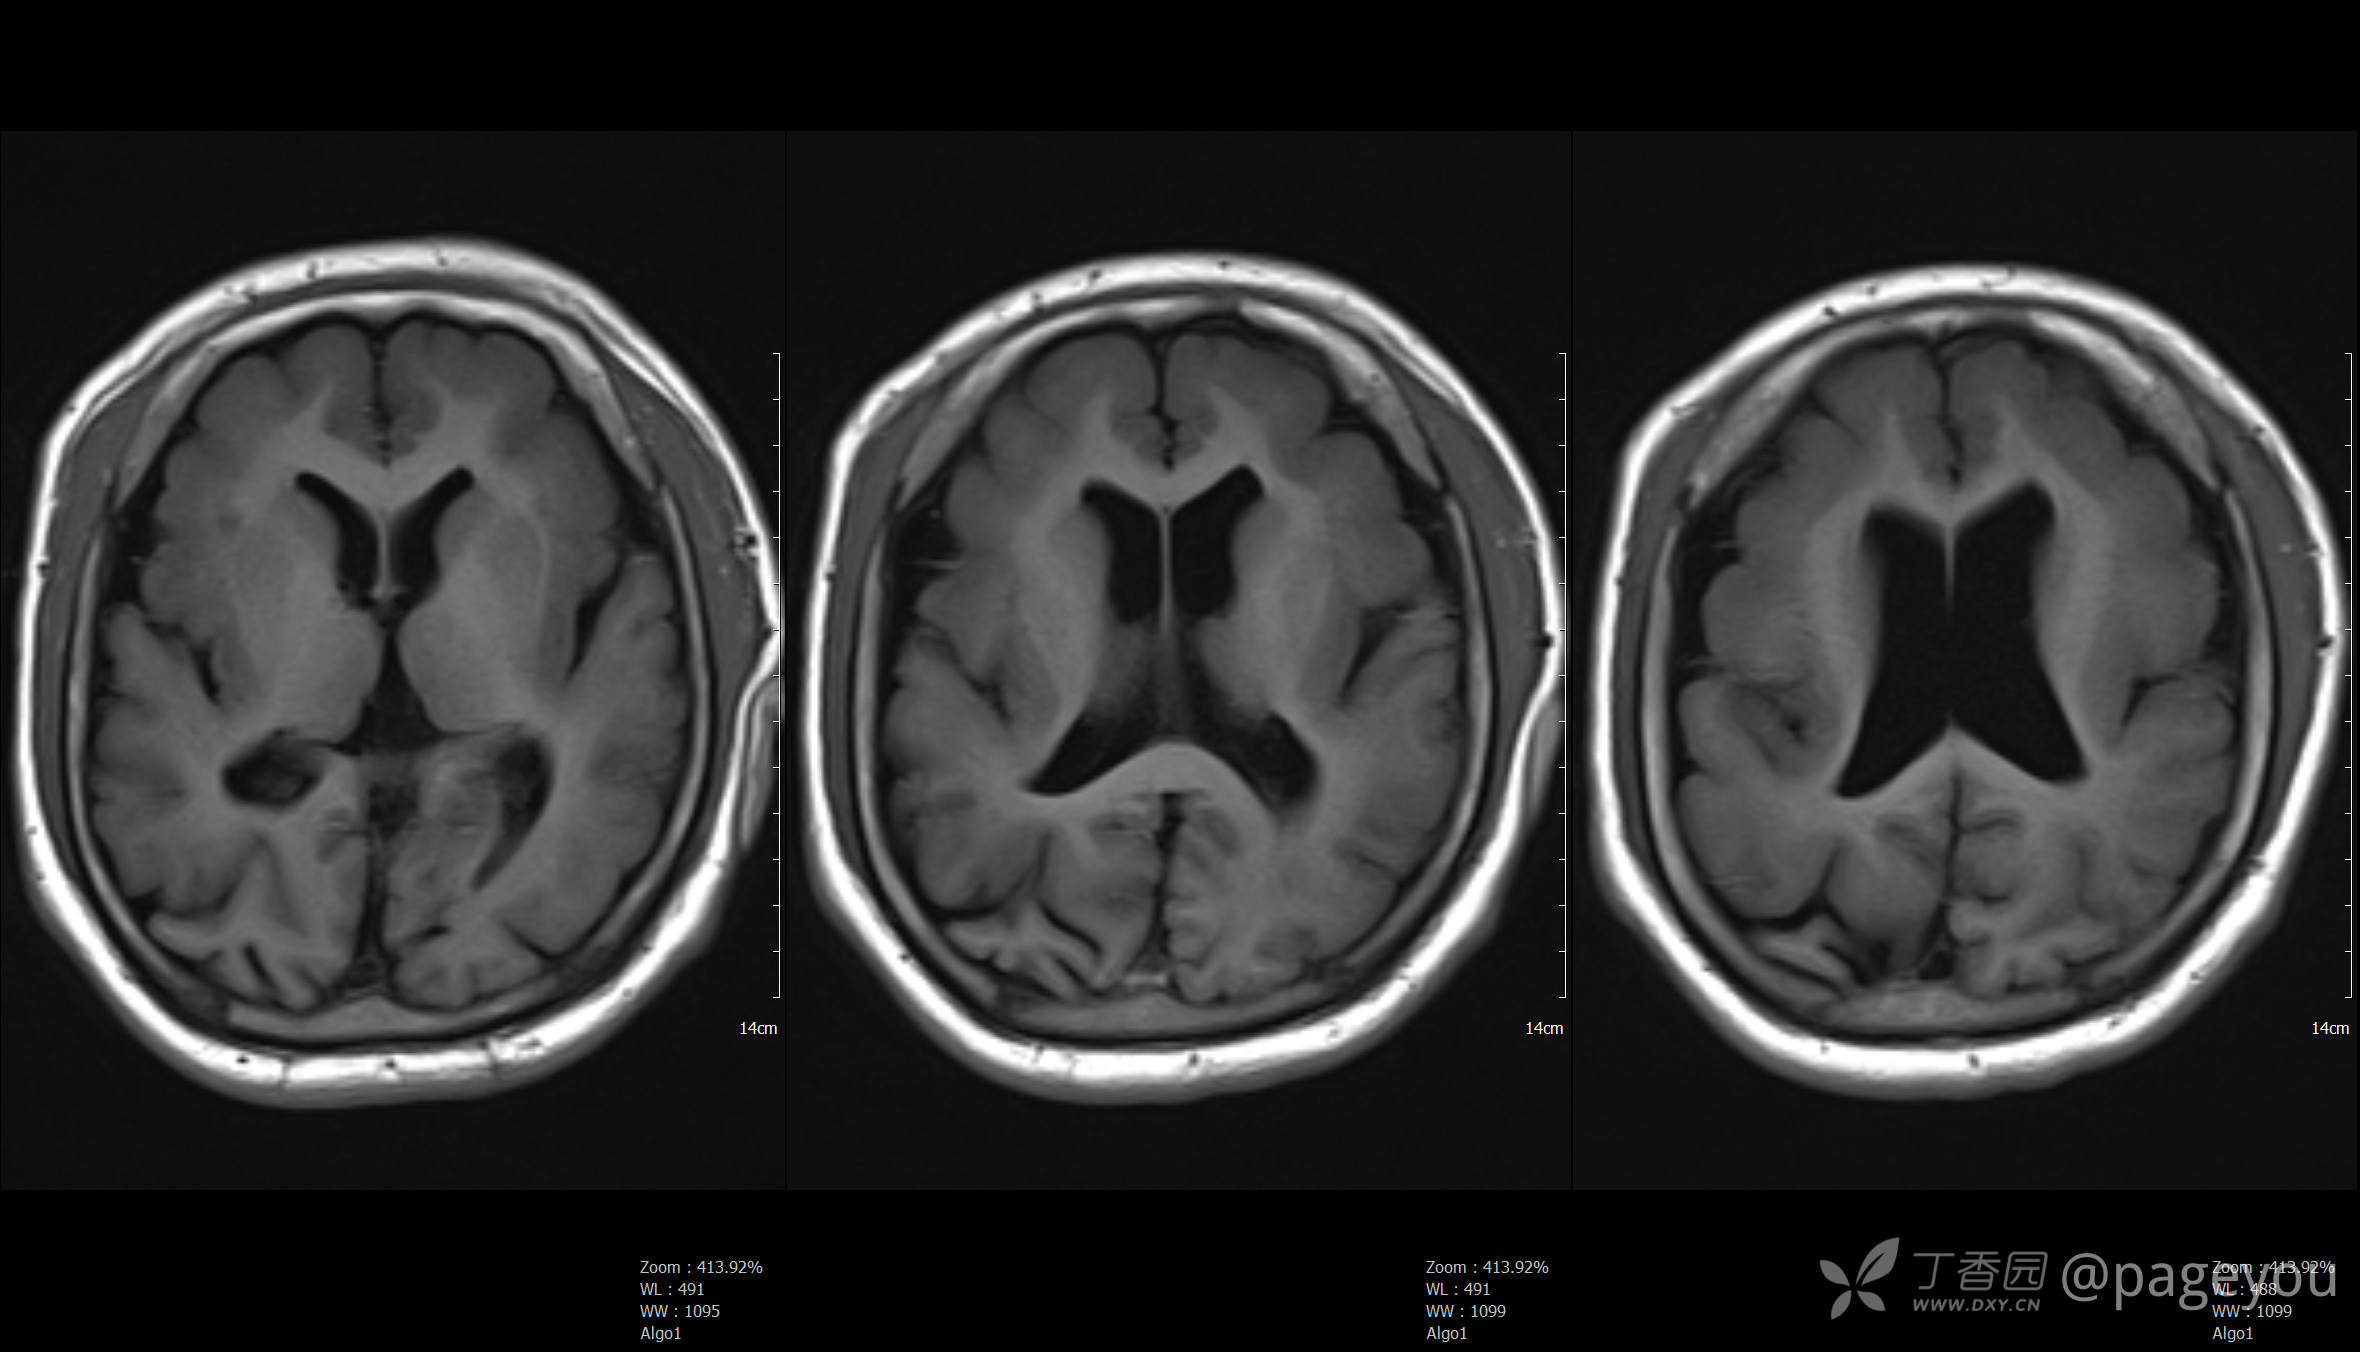

头颅MRI: